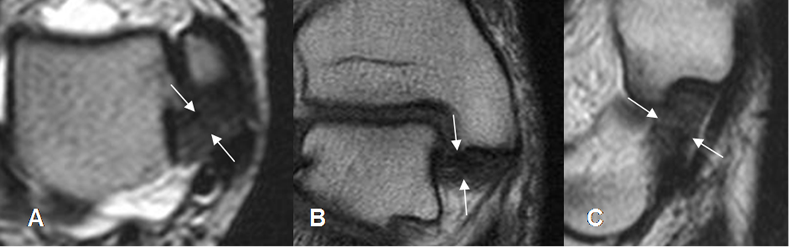

Fig 14. Ligamento tibioastragalino posterior normal.

A: RM axial en T2, B: RM coronal en T2 y C: RM sagital en T1.

Fig 16. Ligamento tibiocalcáneo normal.

A: RM axial y B: RM coronal en T1.

Fig 17. Ligamento calcaneoescafoideo.

A: RM axial en T1 y B: RM sagital en T2. Ligamento hipointenso normal, entre el escafoides y el calcáneo.